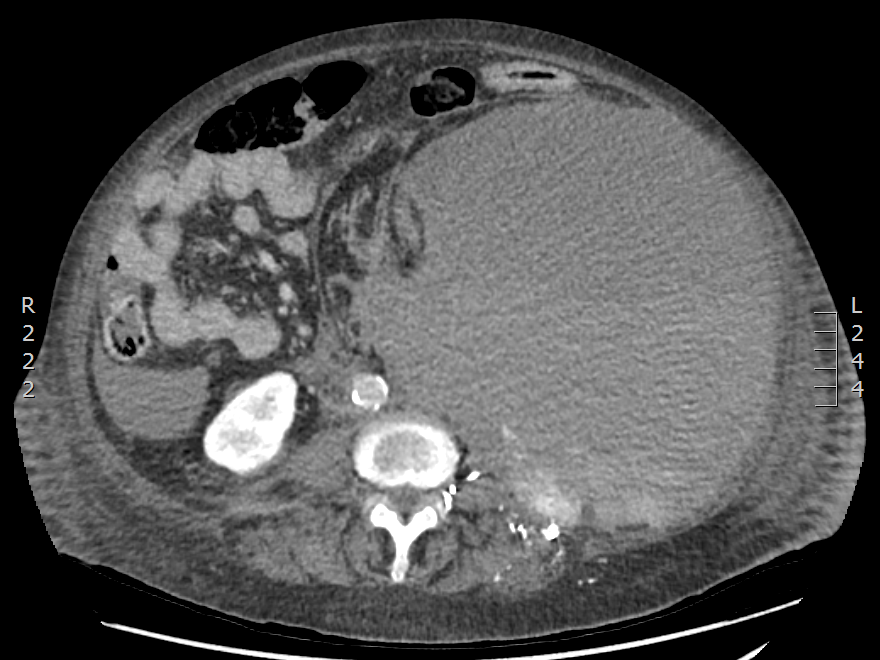

Retroperitoneal Hematoma

Causes

Interventional angiogram identified her primary bleeding source from the left circumflex iliac artery a branch of the external iliac artery and also to a lesser degree from the left L4 and L5 lumbar arteries.

Case Discussion

The patient was emergently transferred to a tertiary center for endovascular embolization. Endovascular angiography revealed the above primary bleeding sources. Each artery received Onyx embolization. Immediate post embolization images showed satisfactory control however her time in ICU continued to be turbulent with dependency on vasoactive medications and continued transfusion of blood products. Repeat abdominal CT angiogram confirmed an increase in the size of her retroperitoneal hematoma. The patient continued to deteriorate falling into multiorgan dysfunction syndrome thought to be contributed by abdominal compartment syndrome. An emergency midline laparotomy was performed. The massive hematoma was evacuated with a rough calculated volume of 10 L. No active arterial bleeding was identified, perhaps from the massive hematoma achieving tamponade. Fortunately, the patient made a full recovery.

Case courtesy of Dr Paul Clarke, Radiopaedia.org, rID: 69556

What are the imaging features of Retroperitoneal Haemorrage?

What are the HU for Acute hemorrhage?

Imaging Features